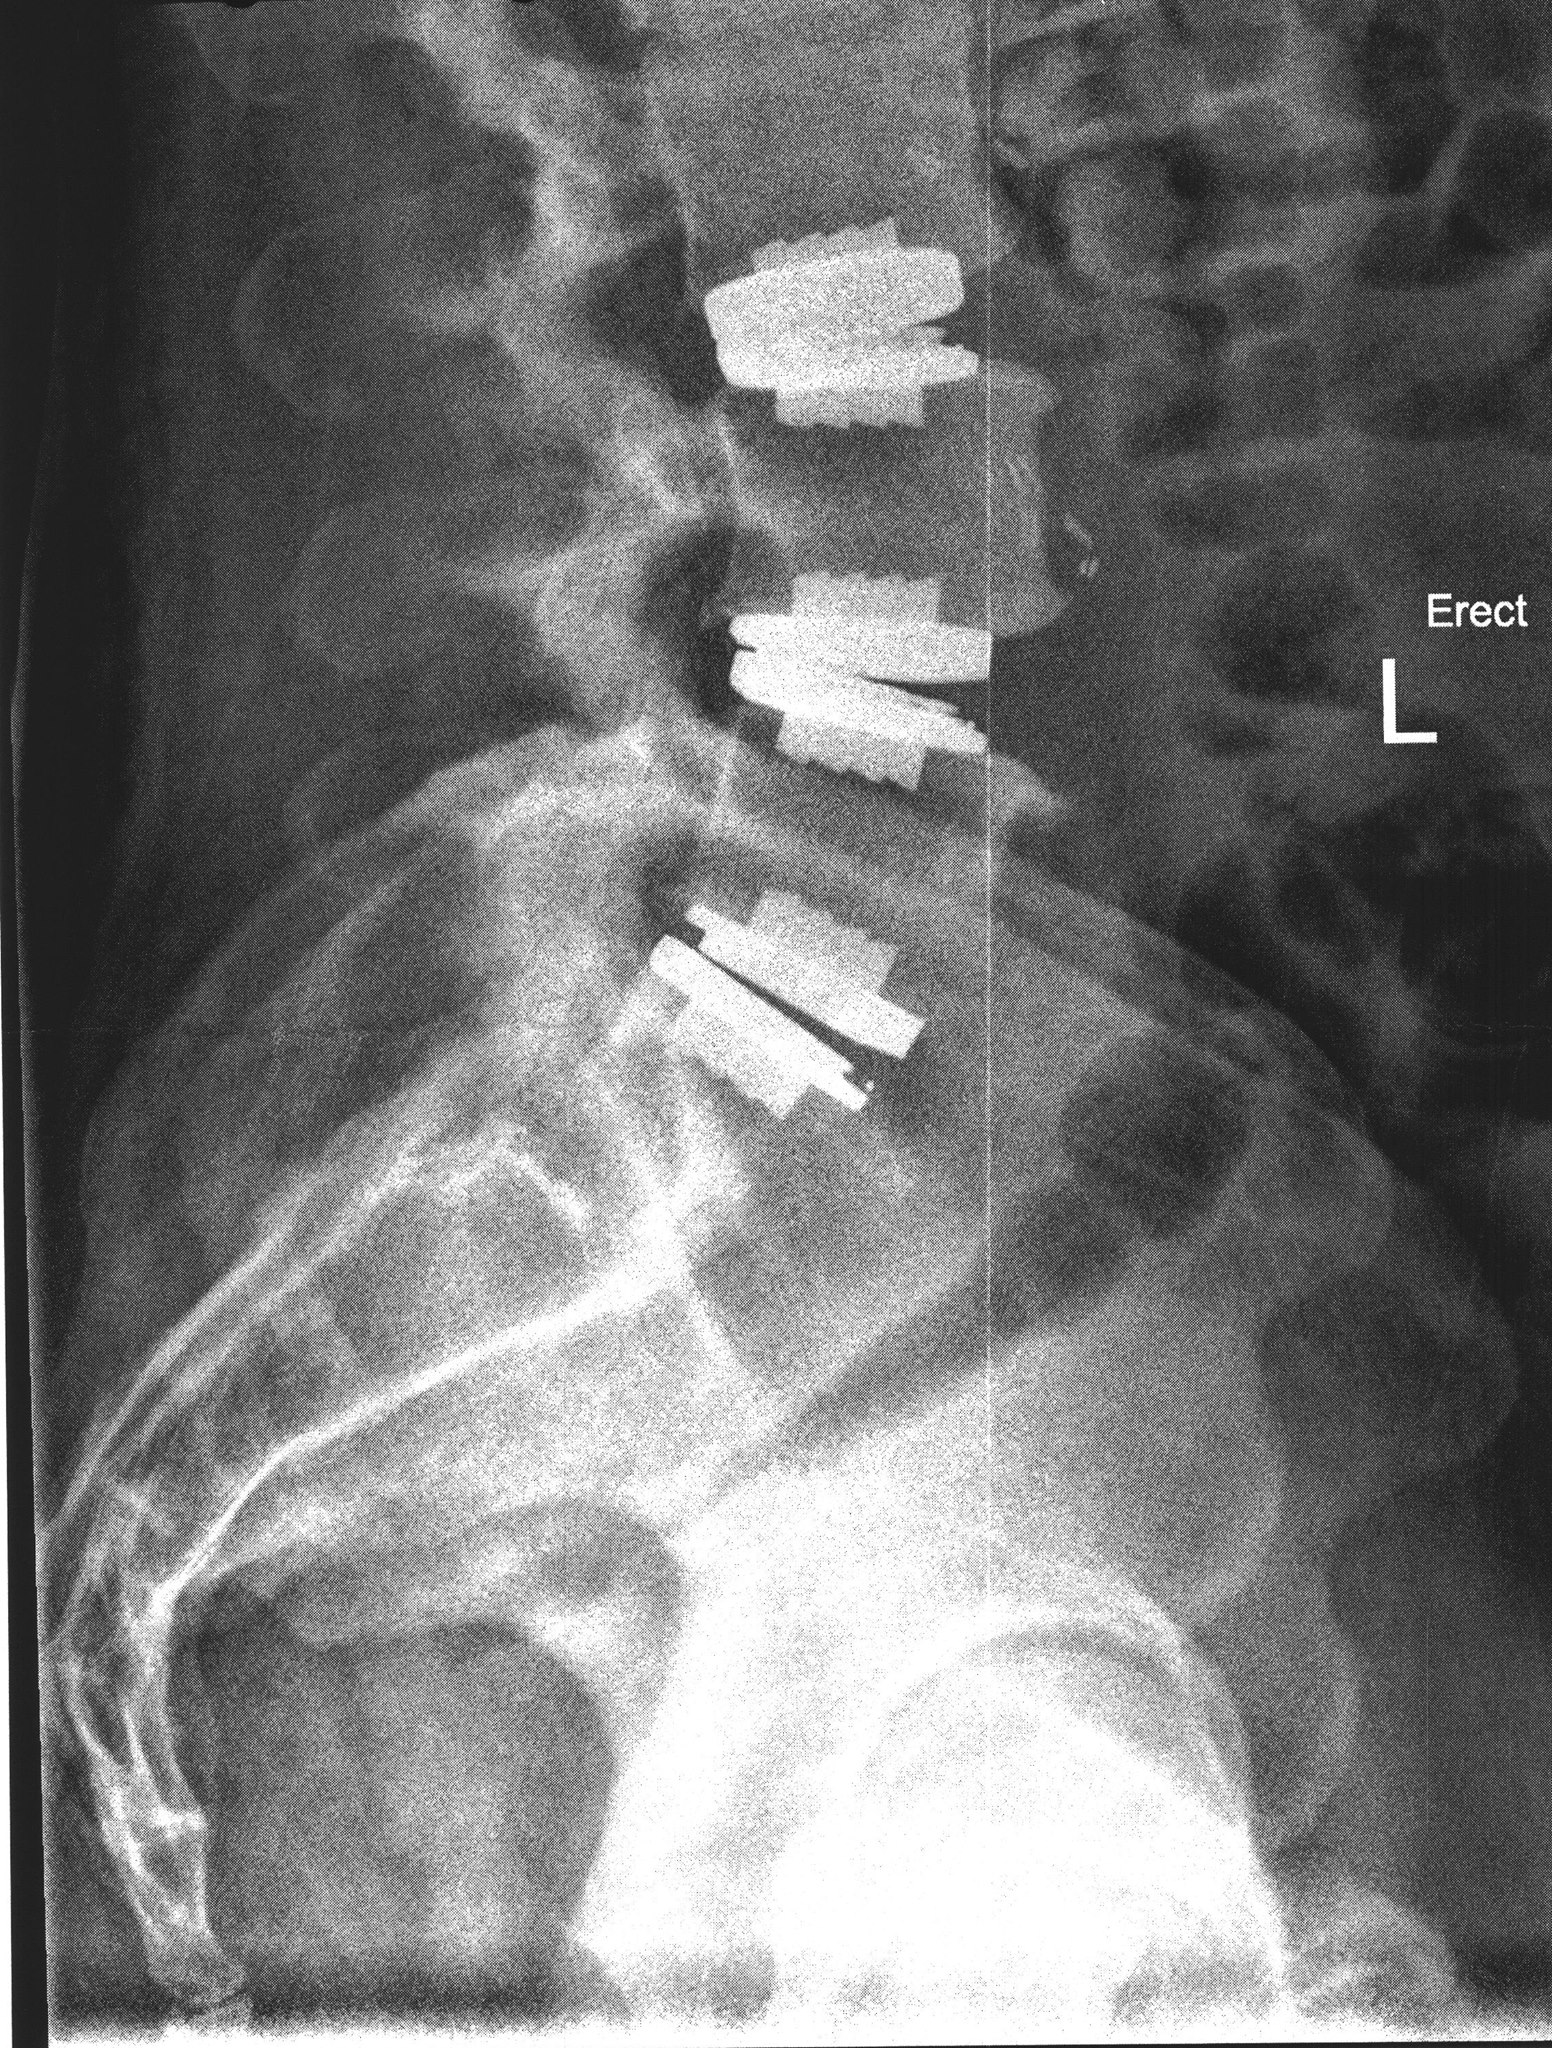

Observation Repair Surgery Bionic Back chuck June 11, 2023 Over the course of a decade from 2010 –...Read More